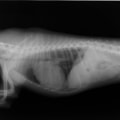

症例:【マルチーズ 12歳齢 去勢オス】

D:胸部レントゲン写真 正面像

E:胸部レントゲン写真 側面像

左側胸壁心尖部領域を最強点とするLevine 5/6の収縮期性心雑音が聴取された。

胸部レントゲン検査において重度の心拡大と肺水腫が認められた。超音波検査では、重度の僧帽弁閉鎖不全症、三尖弁閉鎖不全症、中程度の大動脈弁閉鎖不全症を合併していることが判明した。三尖弁逆流速度から肺高血圧症が示唆された。

ACE阻害薬、ピモベンダン、硝酸イソソルビド徐放剤、ベラプロストナトリウム、利尿剤としてフロセミドとスピロノラクトンを用いて治療を行った。